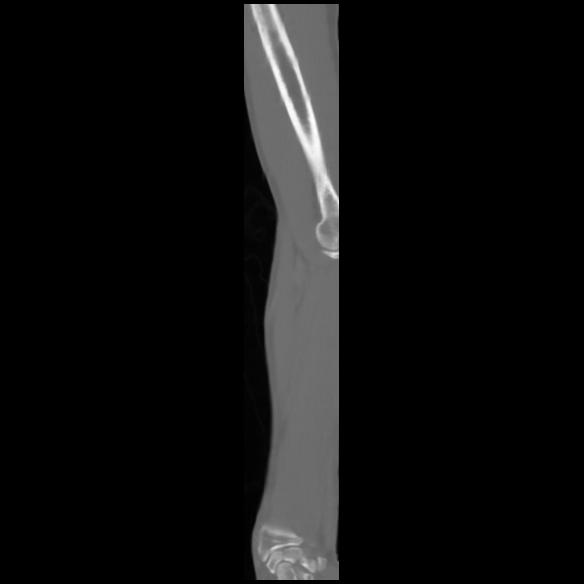

7 CUERPO,CE,Sagittal,3.000,CUERPO,Sagittal,